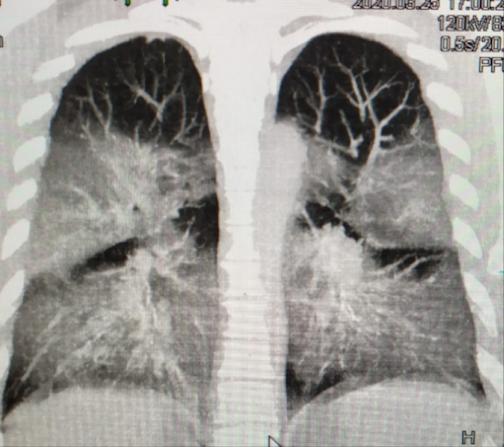

image: COVID-19 and pneumolysis simulating extreme high-altitude exposure with altered oxygen transport physiology.

Initially, all physicians worldwide assumed that the lung affliction in COVID-19 (evidenced by CAT scans and caused by SARS-CoV-2) was the same as in older strains SARS-CoV. However, as fatality rates increased in Intensive Care Units, it became evident that this pathology was entirely new.

The SARS-CoV-2 virus enters the body through inhalation of the viral load, and travels through the bronchi to the surface of the alveoli respiratory sacs where pneumocytes (alveolar lung cells), and their capillaries are located. The pneumocytes allow the diffusion of oxygen molecules to the capillaries where red blood cells capture and transport them to all tissues. They also allow the passage of carbon dioxide molecules (a waste product of respiration) to be exhaled.

The coronavirus intrusion gradually reduces the lung's gas exchange area. This results in alveoli inflammation and a superimposed alteration of lung function similar to High Altitude Pulmonary Edema (HAPE). Both in COVID-19 and HAPE, sea level patients cannot take in enough oxygen as if they were rapidly placed on the summit of Mt. Everest, without time for adaptation. Nevertheless, HAPE is entirely reversible as its mechanism is different, and there is no destruction of alveoli.